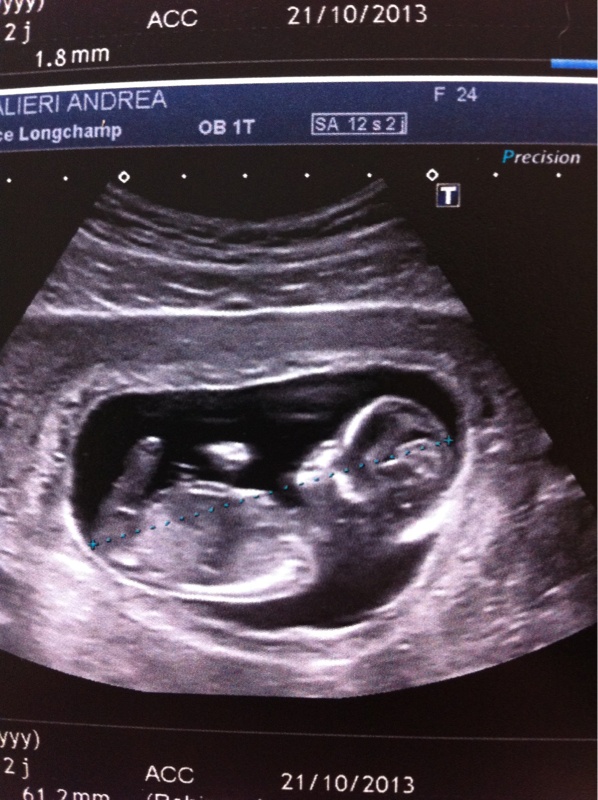

Jsuis de retour de l'écho, tout c'est très bien passé, jvous met une tite photo

Afficher la pièce jointe 576516

Oui trop contente on la bien vu !! Son pti cœur ses ptite mains ses ptite jambes tous y était lol

Bin on a bien vu son petit zizi, mais il nous a quand même dit que ct du 80%, mais bon le zizi est là!!!